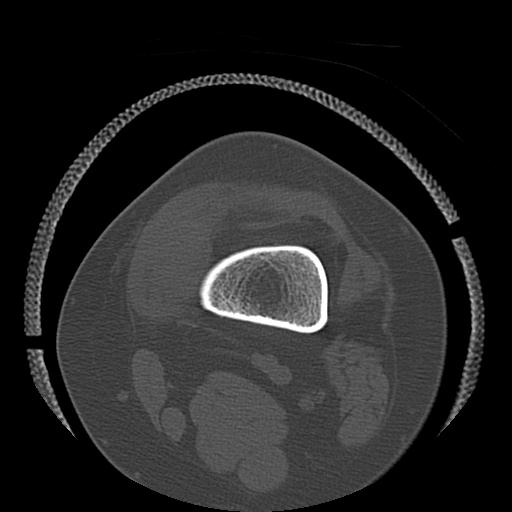

49554 3/13 膝 4R 3/16 4R 1/18 2R 78歳男性 膝蓋骨骨折